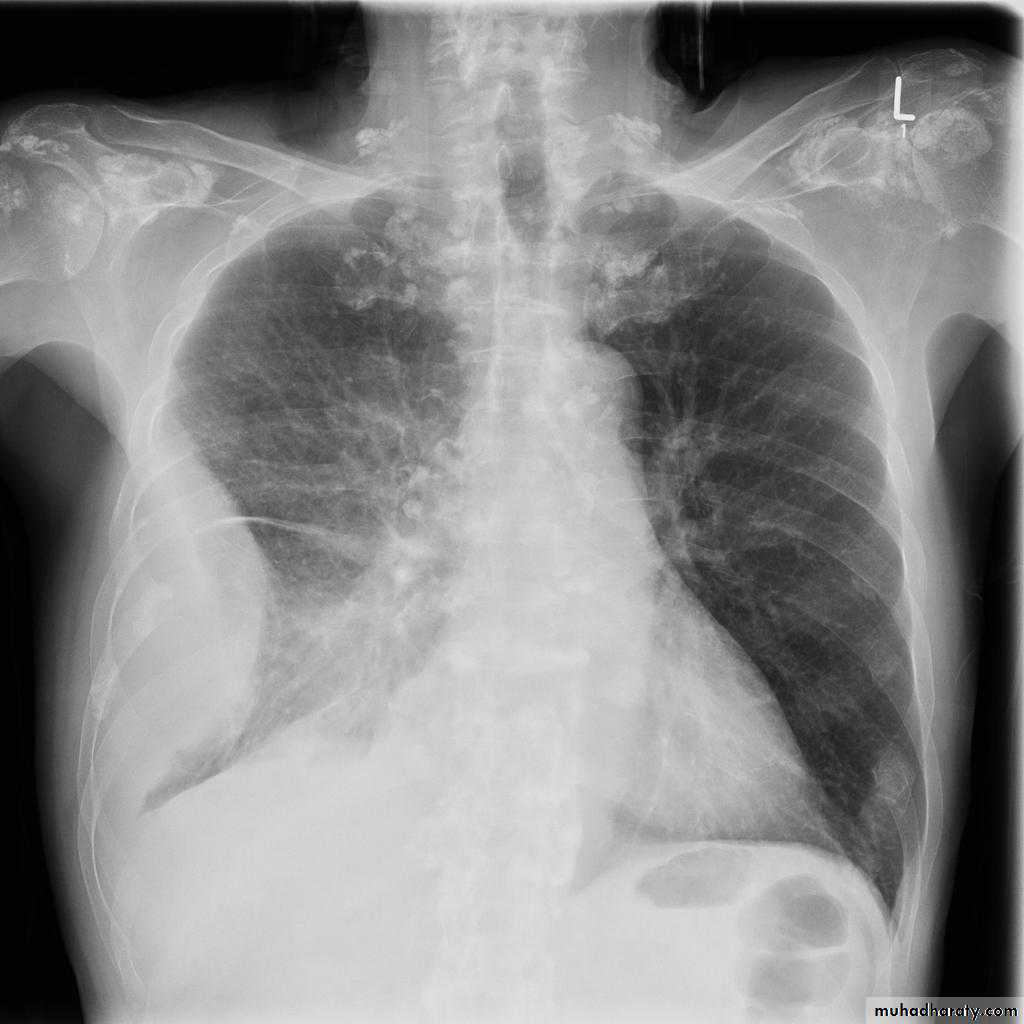

Metastisis to Lung (canon ball appearance)

CXR of adult, PA view shows Bilateral rounded radioopaque nodules of multiple sizes distributed all over both lung fields( Cannon ball appearance)